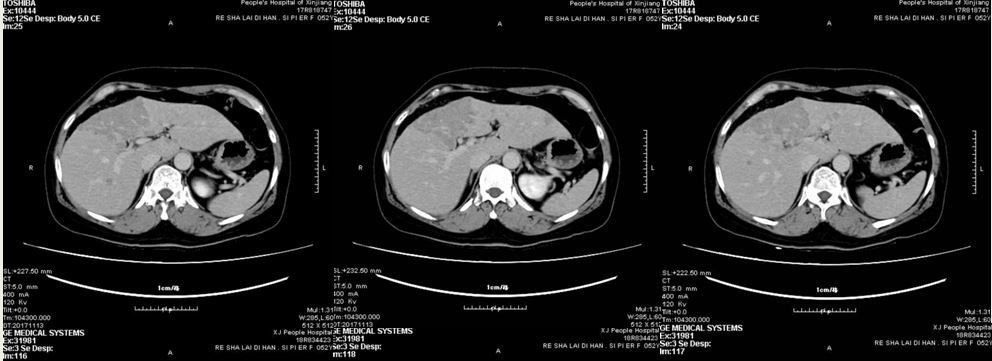

患者完成上述治疗后,定期复查。2017年11月复查腹部B超时发现:肝多发实性占位灶。CT平扫示:肝内多发占位性病变,部分融合成片,考虑转移。行超声引导下肝占位灶穿刺,病理结果提示:转移灶,考虑为乳腺来源。免疫组化 ER(-),PR(-),C-erbB-2(3+)

治疗前肝转移灶

治疗后肝转移灶

患者于2014年2月行右乳腺癌改良根治术,术后确诊为:HER2阳性HR阴性乳腺癌。初始应予以AC-TH一线标准方案辅助化疗,但患者拒绝使用曲妥珠单抗,遂予以AC-T方案。2017年11月发现肝脏转移, 无病生存期(Disease-free  survival,DFS)44个月。复发后行卡培他滨(希罗达)联合曲妥珠单抗靶向抗HER2治疗,迄今为止多次评估,疗效评价完全缓解(complete remission,CR)。截止目前无进展生存期(progression-free survival, PFS)达13个月,未出现疾病进展。